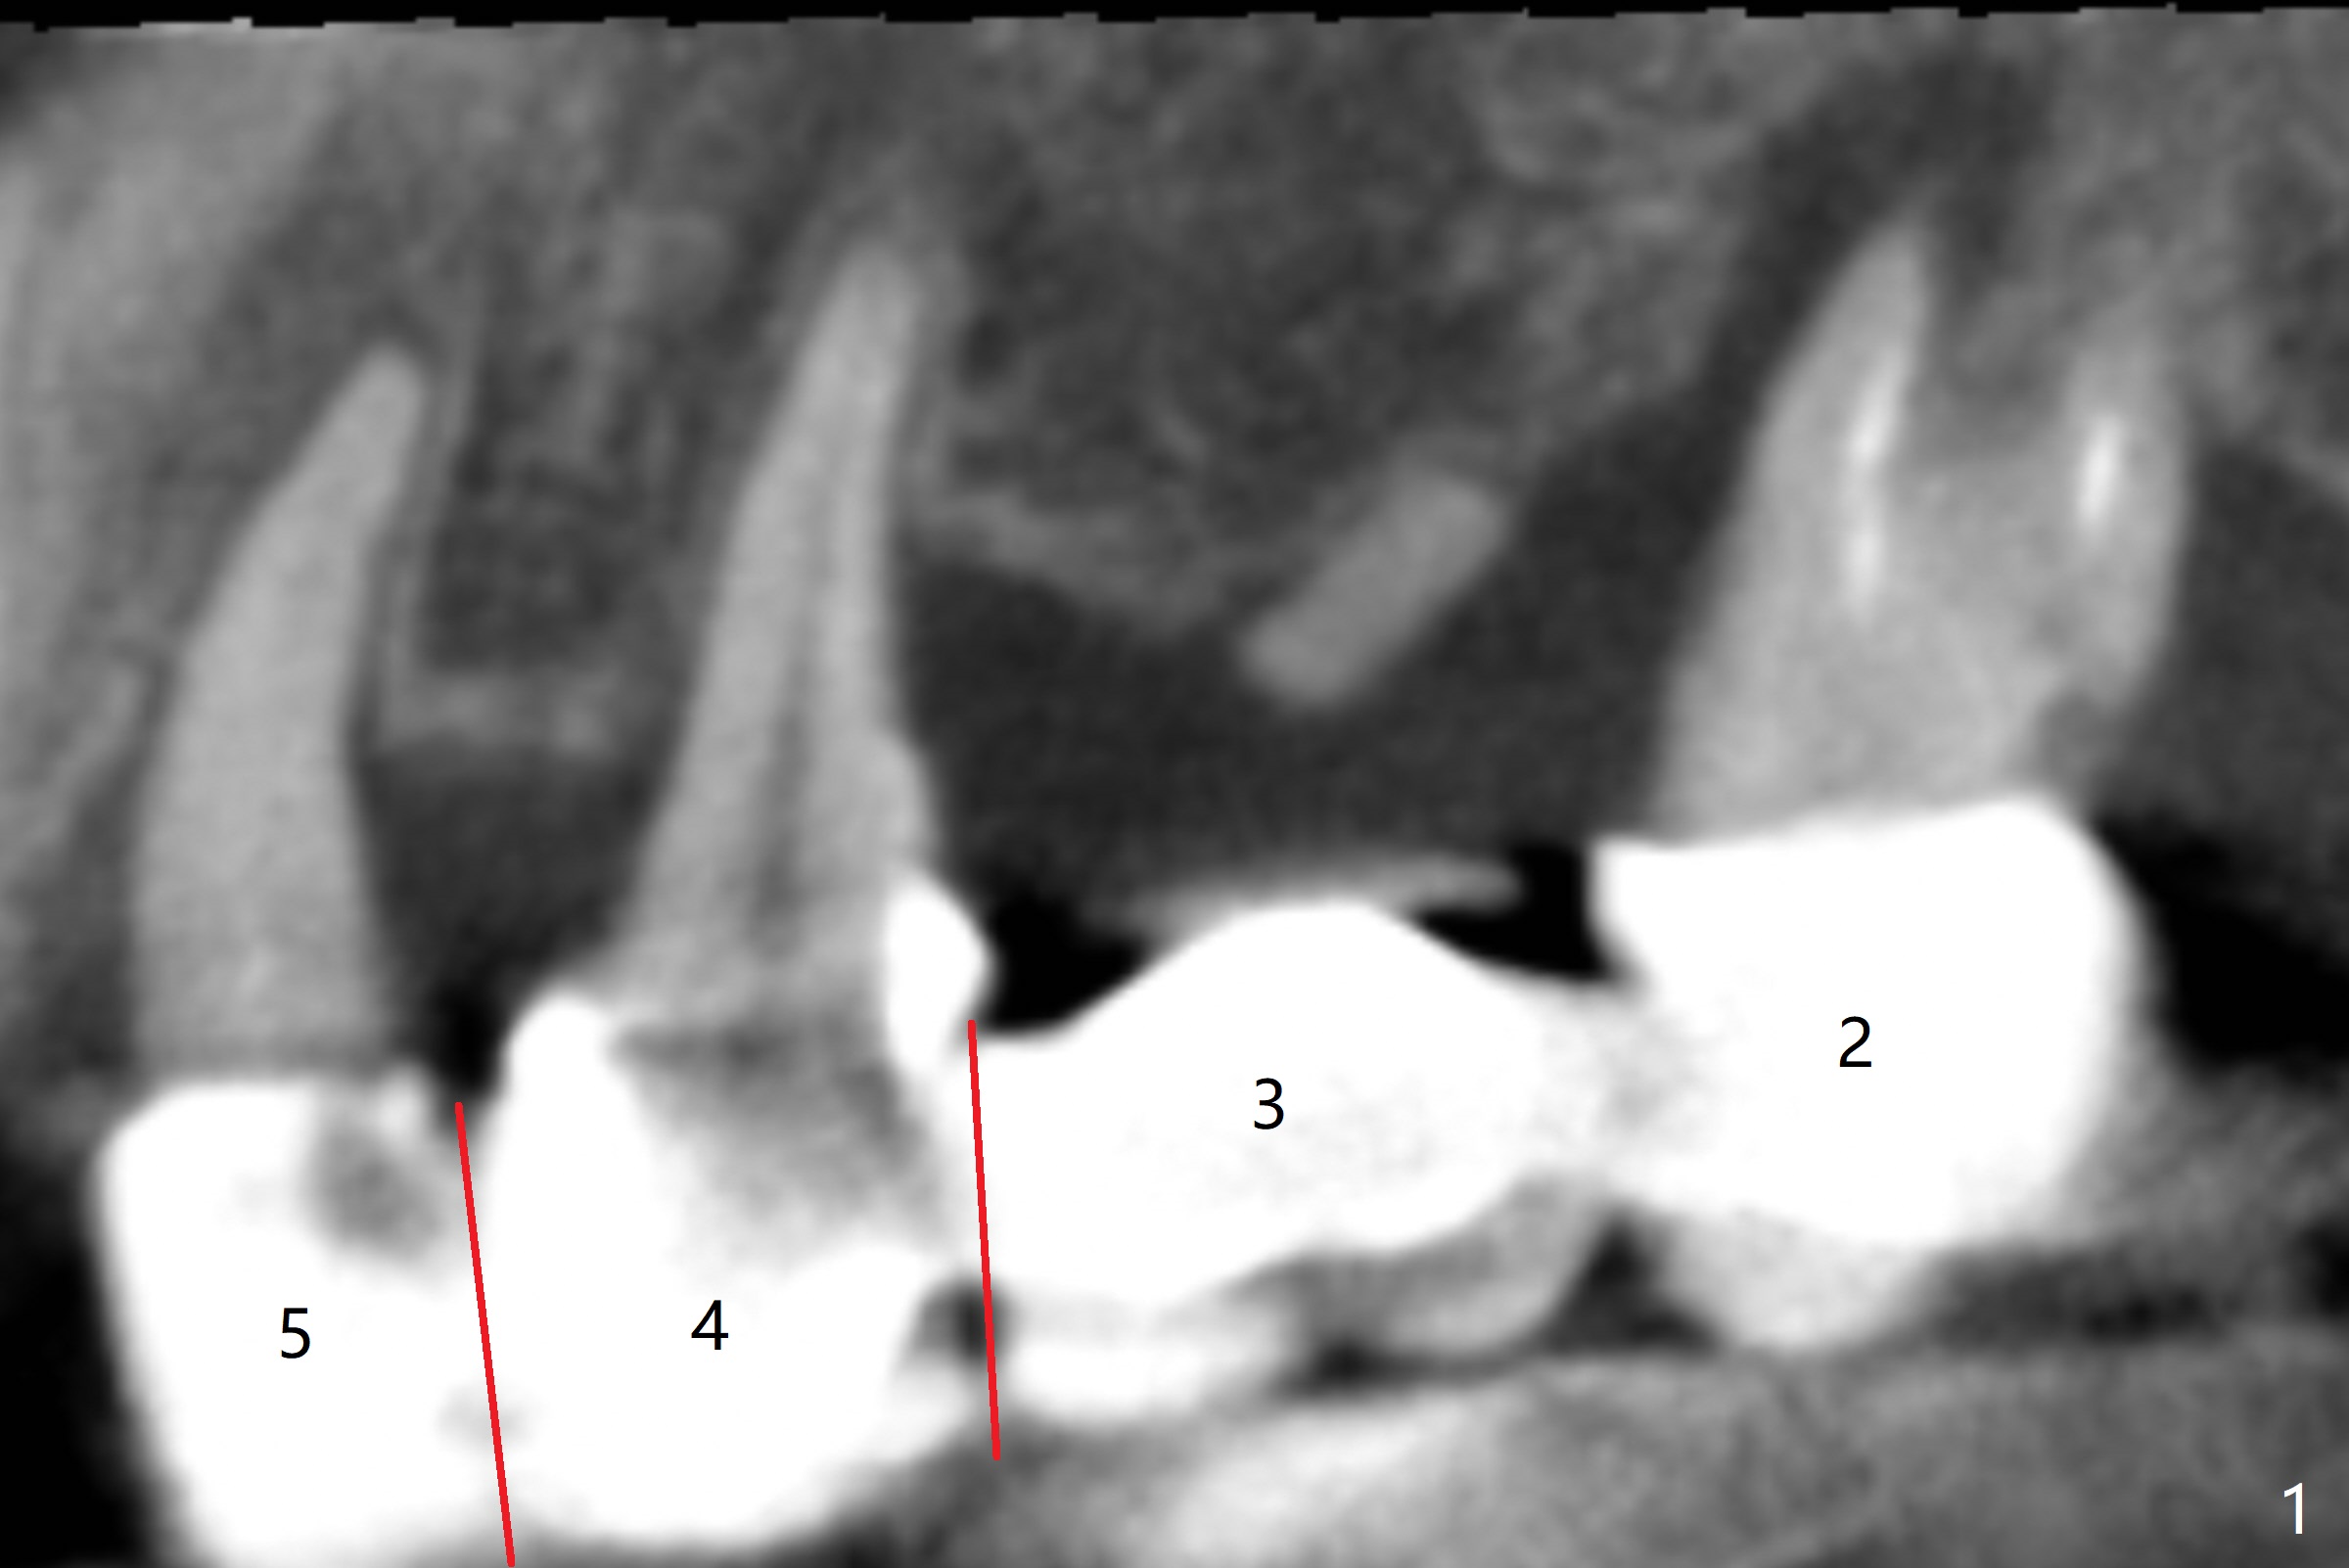

A 43-year-old woman has a failing upper right bridge (Fig.1: #2-5). While the abutment at #5 has apparently palatal open margin (Fig.2,3) and that at #4 has severe palatal bone loss (Fig.4 arrow), that at #2 has the poorest prognosis (Fig.6,7). Panoramic X-ray or PAs will be taken because of CBCT cone cut when the patient returns for #30 and 31 post-implant follow-up. Alginate impression will be taken for the upper right quadrant for provisional. The bridge will be sectioned between #3 and 5 (Fig.1 red lines) to determine salvageability of the abutments at # 4 and 5. If the latter are ok, the abutment at #2 will be extracted (expected to be loose) and implants will be placed at #2 and 3. If #4 is bad while #5 is ok, the former will be extracted and implants will be placed at #2 and 4 with a bridge. If #5 is bad while #4 is ok, implants will be placed at #2, 3 and 5.